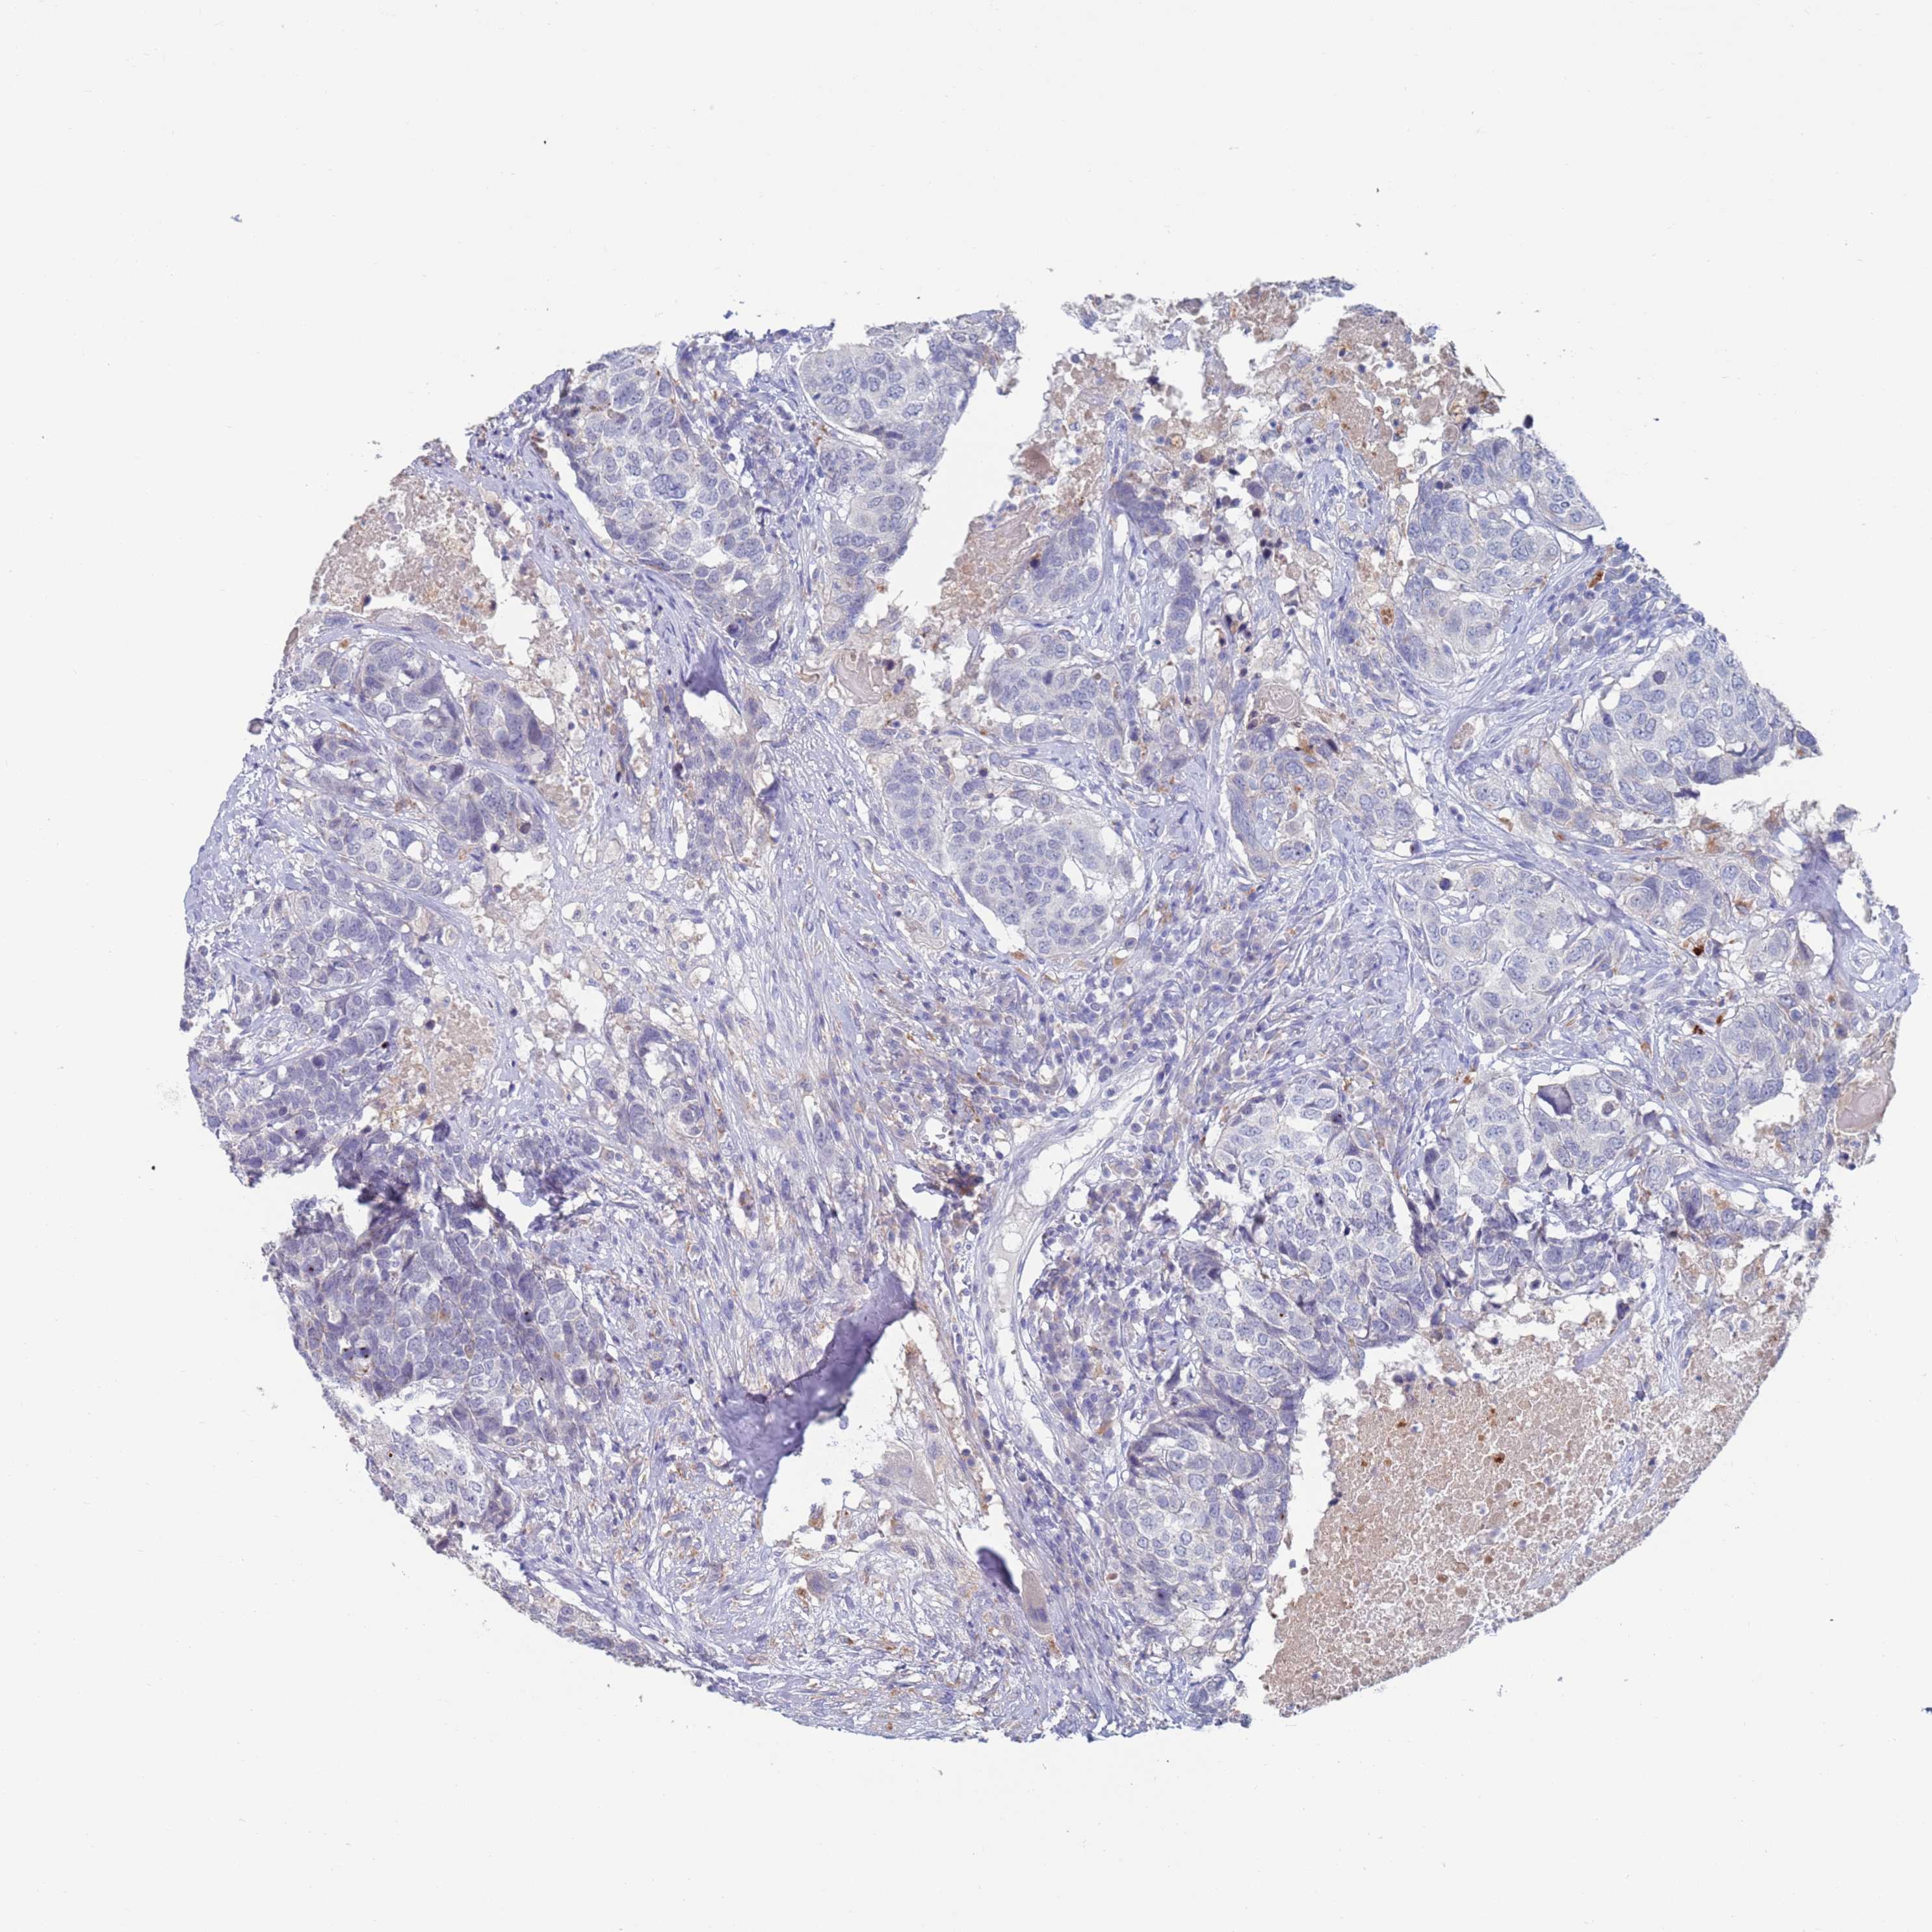

HEAD AND NECK CANCER - Protein expressioni

A mouse-over function shows sample information and annotation data. Click on an image to view it in a full screen mode. Samples can be filtered based on level of antibody staining by selecting one or several of the following categories: high, medium, low and not detected. The assay and annotation is described here.

Antibody stainingi

Antibody staining in the annotated cell types in the current human tissue is reported as not detected, low, medium, or high, based on conventional immunohistochemistry profiling in selected tissues. This score is based on the combination of the staining intensity and fraction of stained cells.

Each image is clickable and will lead to virtual microscopy that enables deeper exploration of all samples and also displays staining intensity scores, fraction scores and subcellular localization as well as patient and tissue information for each sample.

Antibody HPA056371

Staining

High

Medium

Low

Not detected

Intensity

Strong

Moderate

Weak

Negative

Quantity

>75%

75%-25%

<25%

None

Location

Nuclear

Cytoplasmic/membranous

Cytoplasmic/membranous,nuclear

Squamous cell carcinoma, metastatic, NOS